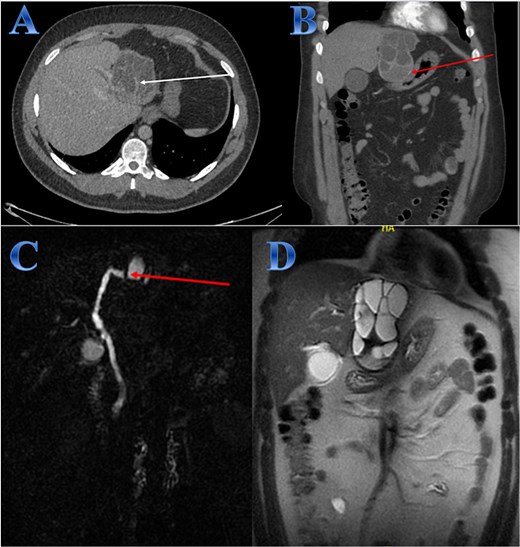

A 54-year-old woman presented with upper abdominal pain with a history of PAIR procedure before 5 years. The abdominal CT scan with contrast highlights left hepatic lobe calcified exophytic CE (Fig. 3).

Case 3. (A) Coronal CT cut of the abdomen at venous phase showing a well-defined cystic lesion (hydatid cyst) seen at the left hepatic lobe, showing calcifications, the lesion seen partially exophytic from the liver and abutting the lesser curvature of the stomach. (B & C) The hydatid cysts that were resected from the liver (C) and from the greater Omentum (B). (D) After resection the liver hydatid cyst was opened to examine the content of the cyst which is showing jelly like structure.

For a left lateral hepatic resection, a subcostal incision allowed exploration of the calcified cystic mass, which affected segments 2 and 3 of the liver and was significantly adhered to the diaphragm and stomach. A left lateral segment (segments 2 and 3) mobilization procedure required dividing the falciform, left triangular, and left coronary ligaments. A harmonic scalpel, in combination with bipolar coagulation, completed the resection of the recurrent hydatid cyst without damaging its internal contents (Fig. 3).